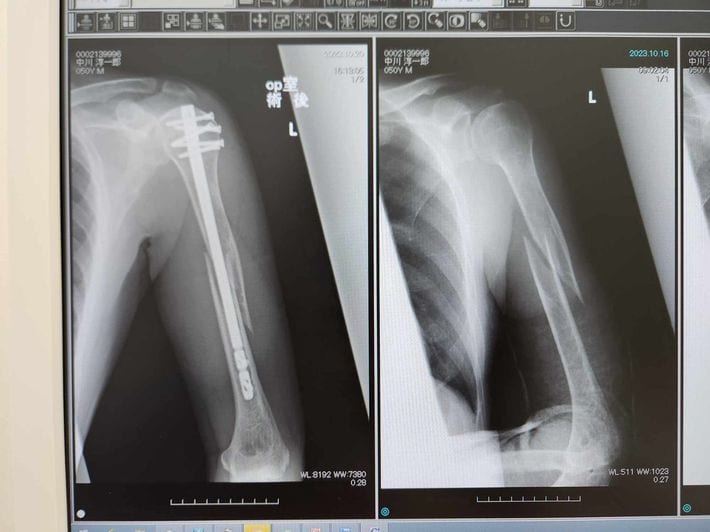

著者の左上腕部レントゲン写真。右が手術前、左が術後。